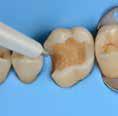

Why deep margin elevation?

Deep margin elevation will make the impression easier by moving the proximal margin of the restoration supra-gingivally, which is especially important for intra-oral scanning. It helps in avoiding periodontal surgical procedures. It makes isolation of the prepared tooth and luting of the final restoration easier.

• Isolation with rubber dam is highly recommended.

• For a better emergence profile, use Teflon tape in the space between the matrix and the adjacent tooth instead of a wedge. Do not use the same matrix as you use for creating a contact point in direct restorations.

• Selective etching of the enamel is recommended.

• Use XBW shade of G-aenial® Universal Injectable for easy differentiation between the tooth, composite material and the restoration.

• The height of the new margin should be slightly above the gingival margin (1mm).

1. Clean the tooth surfaces, rinse thoroughly and dry.

2. Apply a matrix adapted to the technique. Gingival margin of the preparation should be well sealed.

3. Etch the enamel.

5. Dry and light-cure.

6. Apply G-ænial Universal Injectable to the gingival margin of the proximal box.

7. Light cure

8. Remove the matrix and check for

4. Apply a bonding agent (G-Premio BOND or G2-BOND Universal).